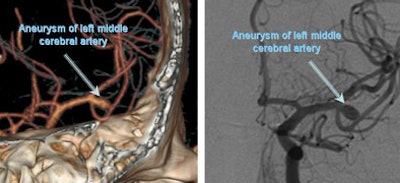

![]() |

| CTA (left) and angiogram (right) shows a single aneurysm of the left middle cerebral artery. Images courtesy of Dr. Charles Prestigiacomo. |